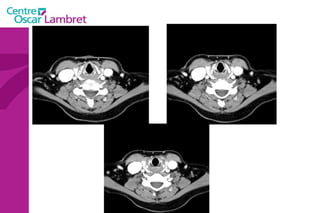

Les Troncs Supra Aortiques s’organisent autour de la trachée à leur origine. L’appareil circulatoire

Le  Tronc artériel Brachio-céphalique  : Naît de la face supérieure du 2e segment horizontal de la crosse aortique à hauteur de T 4. Volumineux, (diamètre 12 mm - longueur 3 cm) il se dirige en haut et à droite croisant la partie droite de la trachée. Derrière l’articulation sterno-claviculaire droite il bifurque en artères sous-clavière droite et carotide primitive droite.  L’appareil circulatoire

Les  artères Carotides Communes  : La droite vient du TABC. La gauche vient de la crosse de l’aorte. Elles n’ont aucune branche collatérale. L’appareil circulatoire

L’artère carotide primitive droite : Elle naît à 3 cm en arrière de l'articulation sterno-claviculaire à la hauteur de T1. monte dans la gouttière carotidienne le long de la trachée et du corps thyroïdien, de l'oesophage puis du larynx et du pharynx.  Elle s’évase avant sa terminaison en regard du bord supérieur du cartilage thyroïde et de C4.  L’appareil circulatoire

L’artère carotide primitive gauche  : naît directement de la crosse aortique et comporte un premier segment intra thoracique en arrière du manubrium sternal. Son segment cervical est identique à celui de la carotide primitive droite.  L’appareil circulatoire